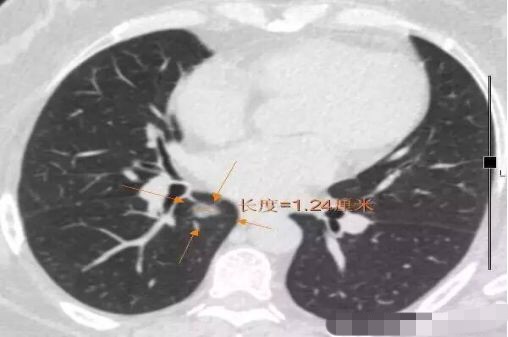

病例1 .

2014年 首次发现右肺上叶GGO,病灶直径8.3毫米, 2016年复查发现右肺上叶GGO,病灶直径12.4毫米。2年大约生长4毫米,平均1年生长2毫米。2016年手术病理结果:浸润性腺癌。

2016年病灶直径12.4毫米